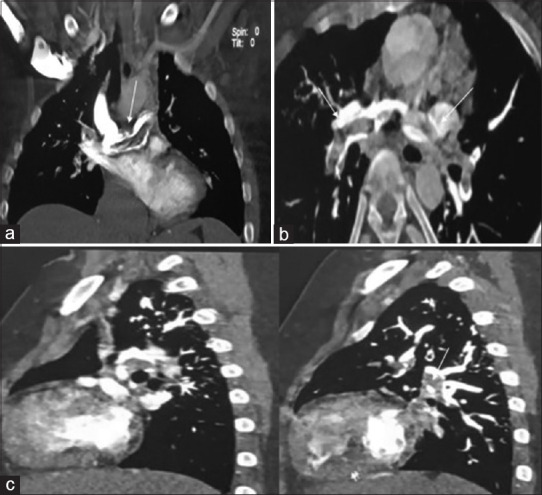

glenn后血栓形成是一种罕见的、需要立即关注的严重并发症,在资源有限的环境中,这种并发症并不罕见,因为患者往往无法随访,并且药物依从性差。这种罕见的并发症在过去很少有报道。我们描述了一个病例的一个巨大的血栓栓塞事件,在病人提出急性失代偿状态14年后,最初的姑息Glenn分流。我们报告了一种创新的策略,使用经导管机械取栓,使用旋转取栓装置和化学溶栓来成功拯救格伦电路。

PostGlenn thrombosis is an infrequent, serious complication requiring immediate attention, which is not uncommon in a resource-limited setting where patients are often lost to follow-up and have poor compliance with medications. This rare complication has infrequently been reported in the past. We describe a case of a massive thromboembolic event in a patient presenting acutely in a decompensated state 14 years after initial palliation by Glenn shunt. We report an innovative strategy of using transcatheter mechanical thrombectomy using a rotational thrombectomy device and chemical thrombolysis for the successful salvation of the Glenn circuit.